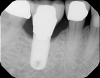

The intraoral orthodontic evaluation showed a class I canine and premolar occlusion on both the right and left sides. The patient had an extensive dental history with multiple fixed prostheses, including both porcelain-fused-to-metal and gold crowns, in the maxillary and mandibular arches. The cement-retained implant crown (No. 30) exhibited 1 mm to 2 mm of mobility in the buccolingual direction. The implant, however, had no signs of acute infection, suppuration, or fistula formation at adjacent and non-adjacent sites (Figure 3).

Fig 3. (Case study 1) Intraoral view of implant No. 30. Peri-implant soft tissue appeared pink and healthy. Visual examination yielded no evidence of inflammation/infection in the area.

Figure 3